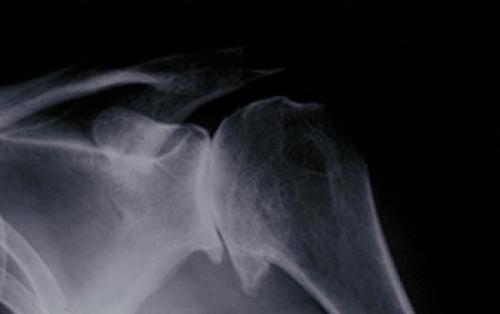

Для точной диагностики артрита плечевого сустава используют методы рентгенографии и компьютерной томографии.

Насколько опасен хруст в плече

Коварство этого часто игнорируемого симптома состоит в том, что за ним могут скрываться сложные патологические процессы в организме . До определенного времени настораживающим симптомом являются хрустящие звуки при движении плеча, в некоторых случаях к ним присоединяется боль.

Оттягивание визита к врачу приводит к прогрессированию течения болезни, его длительному и сложному лечению.

Опасен не хруст сустава, а болезни , симптомом которых он является.

Артриты и артрозы разрушают суставы и нередко приводят к инвалидности больного. Остеохондроз нарушает кровообращение, нервные процессы организма и ощутимо снижает качество жизни.